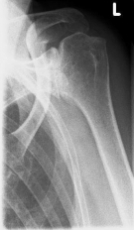

Abbildung2Abbildung1

left: X-ray image of an omarthrosis

right: X-ray of a healthy shoulder joint